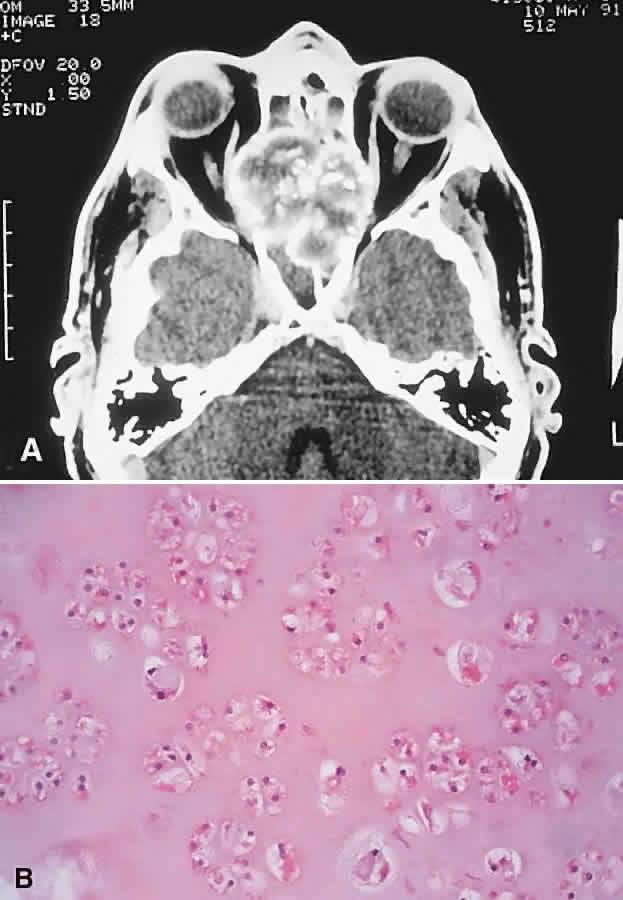

LANGERHANS CELL HISTIOCYTOSIS. Langerhans cell histiocytosis consists of a variety of syndromes resulting from the proliferation of Langerhans cells. Localized bone involvement (eosinophilic granuloma) is prevalent in boys ages 3 to 10 years. These children characteristically develop proptosis as a result of focal lytic superolateral lesions associated with soft tissue expansion.144–146 We have seen six cases of localized Langerhans cell histiocytosis, and each demonstrated a characteristic CT appearance of a central radiolucent area with an enhancing rim (Fig. 12). Histologically, there is a granulomatous and histiocytic infiltrate with Langerhans cells and prominent eosinophils.147 Localized periorbital disease is responsive to curettage, intralesional steroid injections, or low-dose radiation therapy. The prognosis is poorer in younger patients with visceral involvement.

Fig. 12. This 9-year-old boy had a 3-week history of right progressive proptosis associated with inward and downward displacement of the globe. CT demonstrated an osteolytic mass with an enhancing rim destroying the lateral orbital wall. Biopsy revealed Langerhans cell histiocytosis, and he was treated with surgical excision and intralesional steroids. He remains well after 5 years of follow-up. (Rootman J, Stewart BA, Goldberg RA: Orbital Surgery: A Conceptual Approach, p 45. Philadelphia: Lippincott-Raven, 1995.)